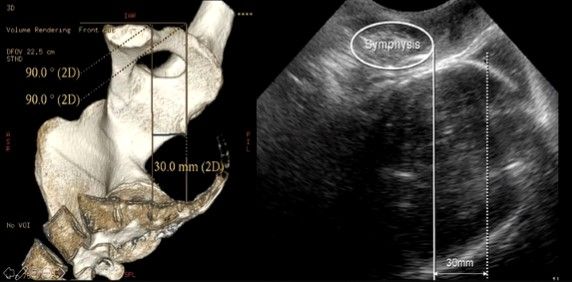

Die Abdominalsonde (mit Kondom überzogen) wird sagittal in der Mittellinie auf die Labien aufgesetzt um den AOP zu messen. Die Symphyse wird im Längsschnitt ca. mittig im Bild schallkopfnahe abgebildet (s. Bild oben).

Angle of progression/descent

- Winkelfunktion am Ultraschallgerät einstellen

- Legen einer Waagrechten mittig durch die Symphyse bis zur Unterkante (CAVE nicht nur bis zum Ende des hyperechogenen Kerns) (s. Bild).

- Winkel zur Schädelkalotte ziehen (CAVE nicht bis zum Caput succedaneum) = AOP

Head station - Höhenstand

- Höhenstand in Bezug zur Interspinalebene

- Senkrechte durch die Unterkante der Symphyse

- 3cm kaudal davon Parallele: geht durch Interspinalebene. Diese entspricht ITU-Höhenstand = 0

- Höhenstand als Abstand zwischen Paralleler durch Interspinalebene und tiefstem knöchernen Kopfanteil in cm kann bestimmt werden